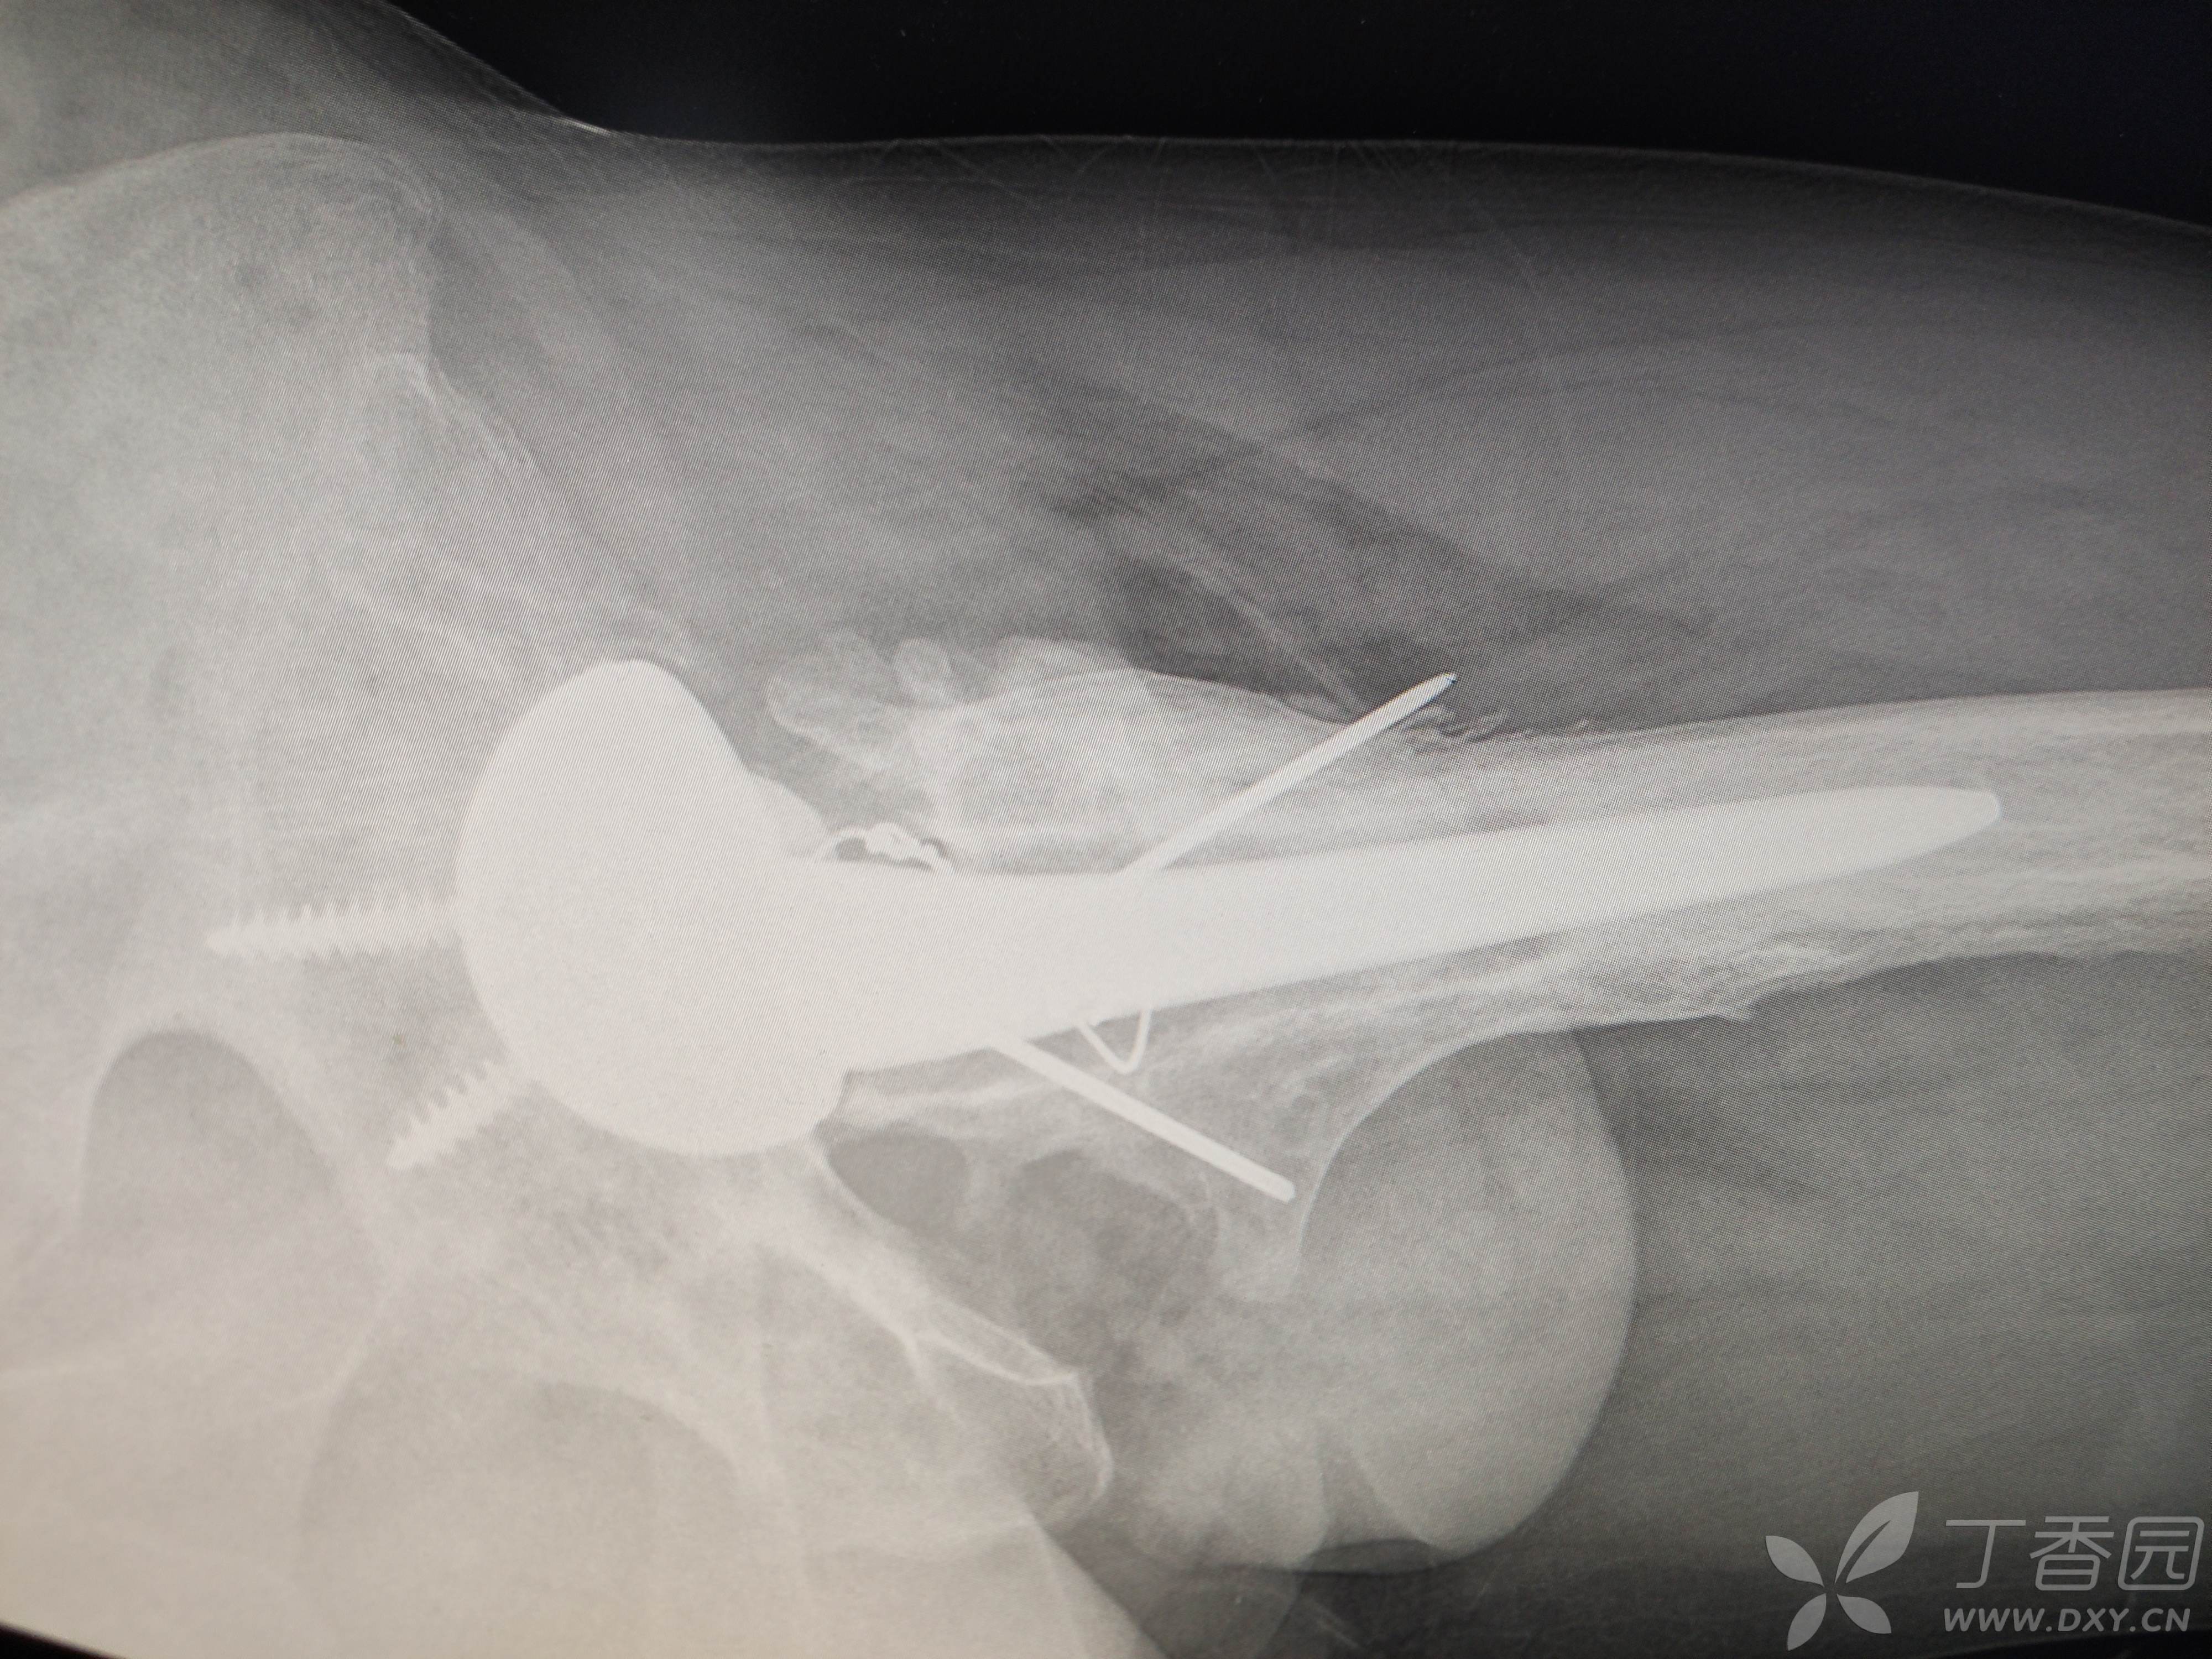

髋关节置换术后12年,大腿前内侧窦道1年,再发2周

患者12年因车祸伤致左股骨头粉碎性骨折,行左侧髋关节置换术,术后伤口愈合良好,左下肢轻度跛行,行走尚可,无疼痛。

辅助检查:近期的ESR(血沉) 32mm/h↑,hsCRP(高敏C反应蛋白) 25.55mg/L↑,PCT(降钙素原)0.03ng/ml,正常。血常规正常。X线片及CT是近期的。12年前的影像资料缺失。